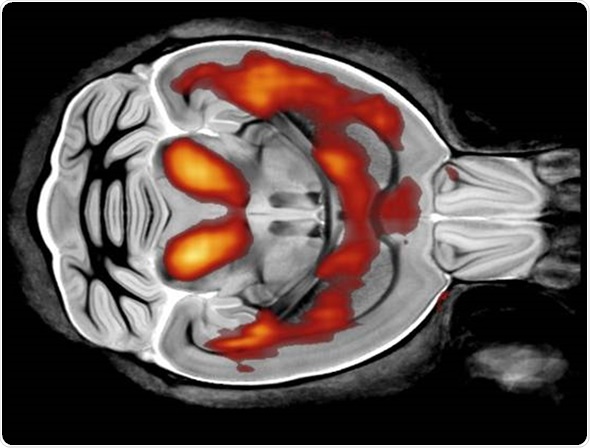

Each modality looks at tissue in a different way. For example, MRI has very good soft tissue contrast and there is a number of parameters that are associated with different pathologies.

For example, there are T1 and T2 changes in cancer and neurodegenerative diseases, whereas, with a modality like CT, there's less soft tissue contrast and it would be used more to look at things like bone structure. It uses a different type of contrast and produces images through a different physical mechanism.

By using different modalities, we can get much more information compared with using only one modality.

The MRI has a very good soft tissue contrast. The parameters that I generally look at using MRI are called T1 and T2. These vary in different tissues, obviously, but also across different pathologies. MRI provides very high sensitivity to these pathologies, which can't be seen using other modalities.